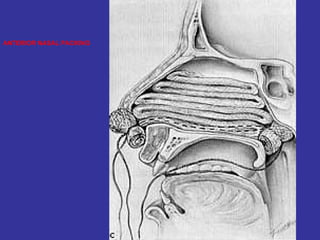

In the sides of the nasal septum, there is 3 shelf-like structures where discharge is drain and is called  Turbinates  MAXILLARY ANT. ETHMOID  MIDDLE MEATUS FRONTAL POST. ETHMOID   SUPERIOR MEATUS SPHENOID LACRIMAL DUCTS   INFERIOR MEATUS (Largest and most visible)

PHYSIOLOGY: Usually after URI   Mucosal edema   ↓   mucus transport    obstruction  of osteomeatal complex   stagnation of secretions    ↓  of pH/decrease O2 tension within the sinus   promotes  Bac/Viral growth. THREE KEY ELEMENTS: PATENCY OF THE OSTIA FUNCTION OF THE CILIARY APPARATUS QUALITY OF SECRETIONS -Patency of the Ostia:  Mucosa Edema: allergy, viral  Mechanical Obstruction: Obstruction of meatus  Deviated nasal septum -The function of the ciliary apparatus:  Help nose filter bacteria/pollutant Help regulate temp/humidification -Quality of secretions:  Hypersecretion   obstruction   less O2   growth of bacteria,  impairs defenses, and alters the function of immune cells.